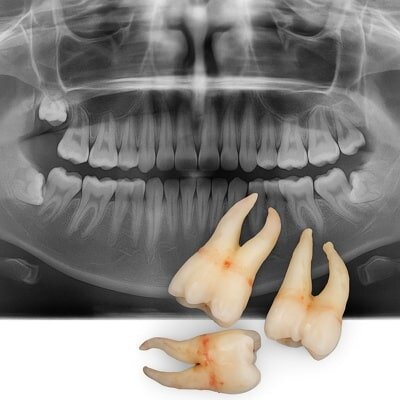

دندان عقل نهفته با دندان عقل معمولی تفاوت زیادی در روش درمان و در نتیجه هزینه دارد. در حالت نهفته، دندان زیر لثه یا داخل استخوان فک قرار دارد و برای خارج کردن آن نیاز به کشیدن دندان عقل جراحی، برش لثه، استفاده از ابزار تخصصی و بخیه وجود دارد.

همین مراحل باعث میشود هزینه کشیدن دندان عقل نهفته معمولاً بین ۲ تا ۳ میلیون تومان باشد.

در مقابل، کشیدن دندان عقل معمولی یا رویشیافته معمولاً سادهتر است و اغلب با بیحسی موضعی و بدون جراحی انجام میشود؛ بنابراین هزینهای در حدود ۱ تا ۱٫۵ میلیون تومان دارد. تفاوت قیمت در واقع ناشی از زمان بیشتر جراحی، نیاز به تجهیزات پیشرفته و مهارت جراح فک و دهان است.

البته در کلینیکهای تخصصی دندانپزشکی تهران که از دستگاههای دیجیتال و سیستمهای تصویربرداری سهبعدی استفاده میکنند، هزینهها منطقیتر بوده و درعینحال نتیجهٔ درمان ایمنتر و بدون عارضه خواهد بود.